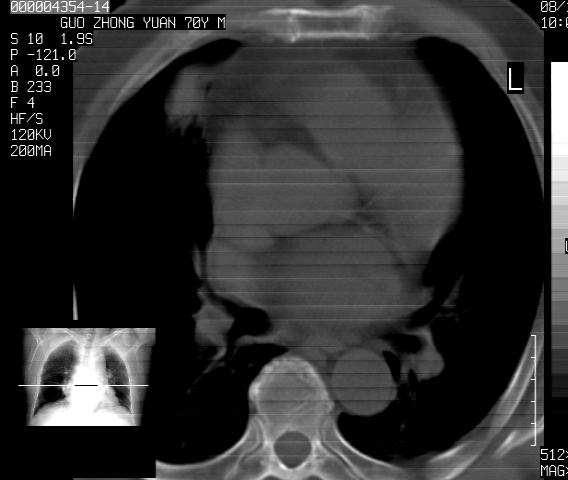

以下是引用sdzyy在2008-12-1 11:49:00的发言:[br]图像不全,请上传,右下肺炎症可能性大,占位待排.

以下是引用zjzjr在2008-12-1 14:53:00的发言:[br]图像不全,请上传,右下肺炎症可能性大,占位待排.心影增大,建议进一步检查.